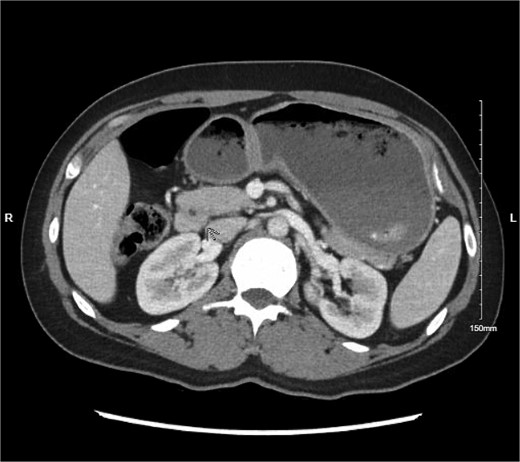

Physical exam was significant for epigastric and bilateral upper quadrant abdominal tenderness without guarding. Notably, her urinalysis was positive for ketones. Abdominal CT with intravenous contrast ordered in the emergency department revealed a near complete annular pancreas at the level of the first portion of the duodenum with concurrent gastric and duodenal bulb distension with no evidence of pancreatitis (See Fig. 1). Nasogastric tube decompression and antiemetic therapy were initiated, and the patient underwent magnetic resonance cholangiopancreatography (MRCP), which revealed severe duodenal narrowing at the second portion with circumferential encasement of the pancreas (See Fig. 2).

Abdominal CT with IV contrast showing fluid distension of the stomach and duodenal bulb with encirclement of pancreatic tissue around the first portion of the duodenum.